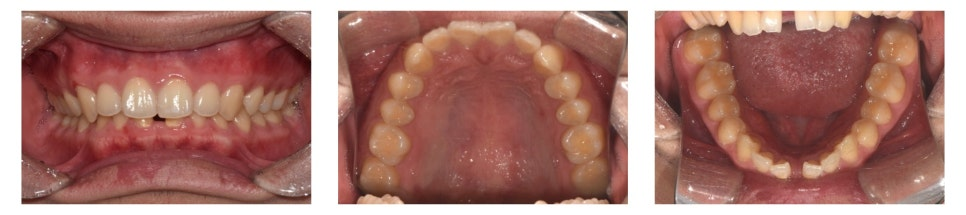

만 21세 남자 환자가 아래 앞니가 벌어졌다는 고민으로 찾아왔습니다.

초진 구내 사진을 보면,

▶ 아래 앞니 사이가 많이 벌어진 상태(spacing)

▶ 앞니가 깊게 물려 있는 상태(deep bite)

를 확인할 수 있었습니다.